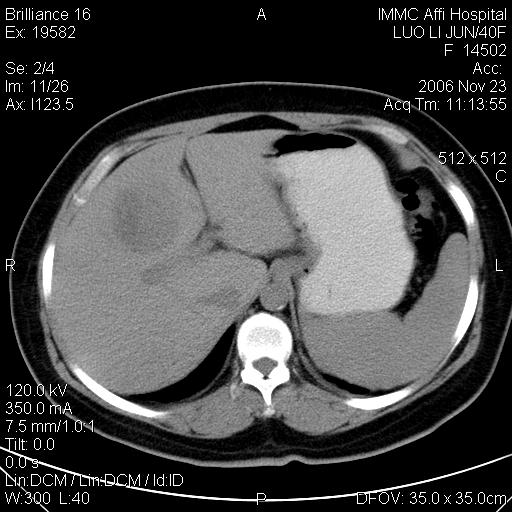

标题: CT5664:我也发一个肝脏的片子大家看看

很典型的肝癌。

典型肝癌

肝癌

速升速降,典型肝癌.

典型肝癌.

是啊,典型的早出早归!

快进快出典型肝癌.

符合肝癌的增强特征。支持肝癌!

病灶好圆!可能恶性度不高。

不能除外肝细胞腺瘤吧,还是得结合病史。

很好的片子,可惜增强做的比较失败,a期时间没有把我好,实际到了静脉早期了,否则会更典型。

最终考虑是肝腺瘤